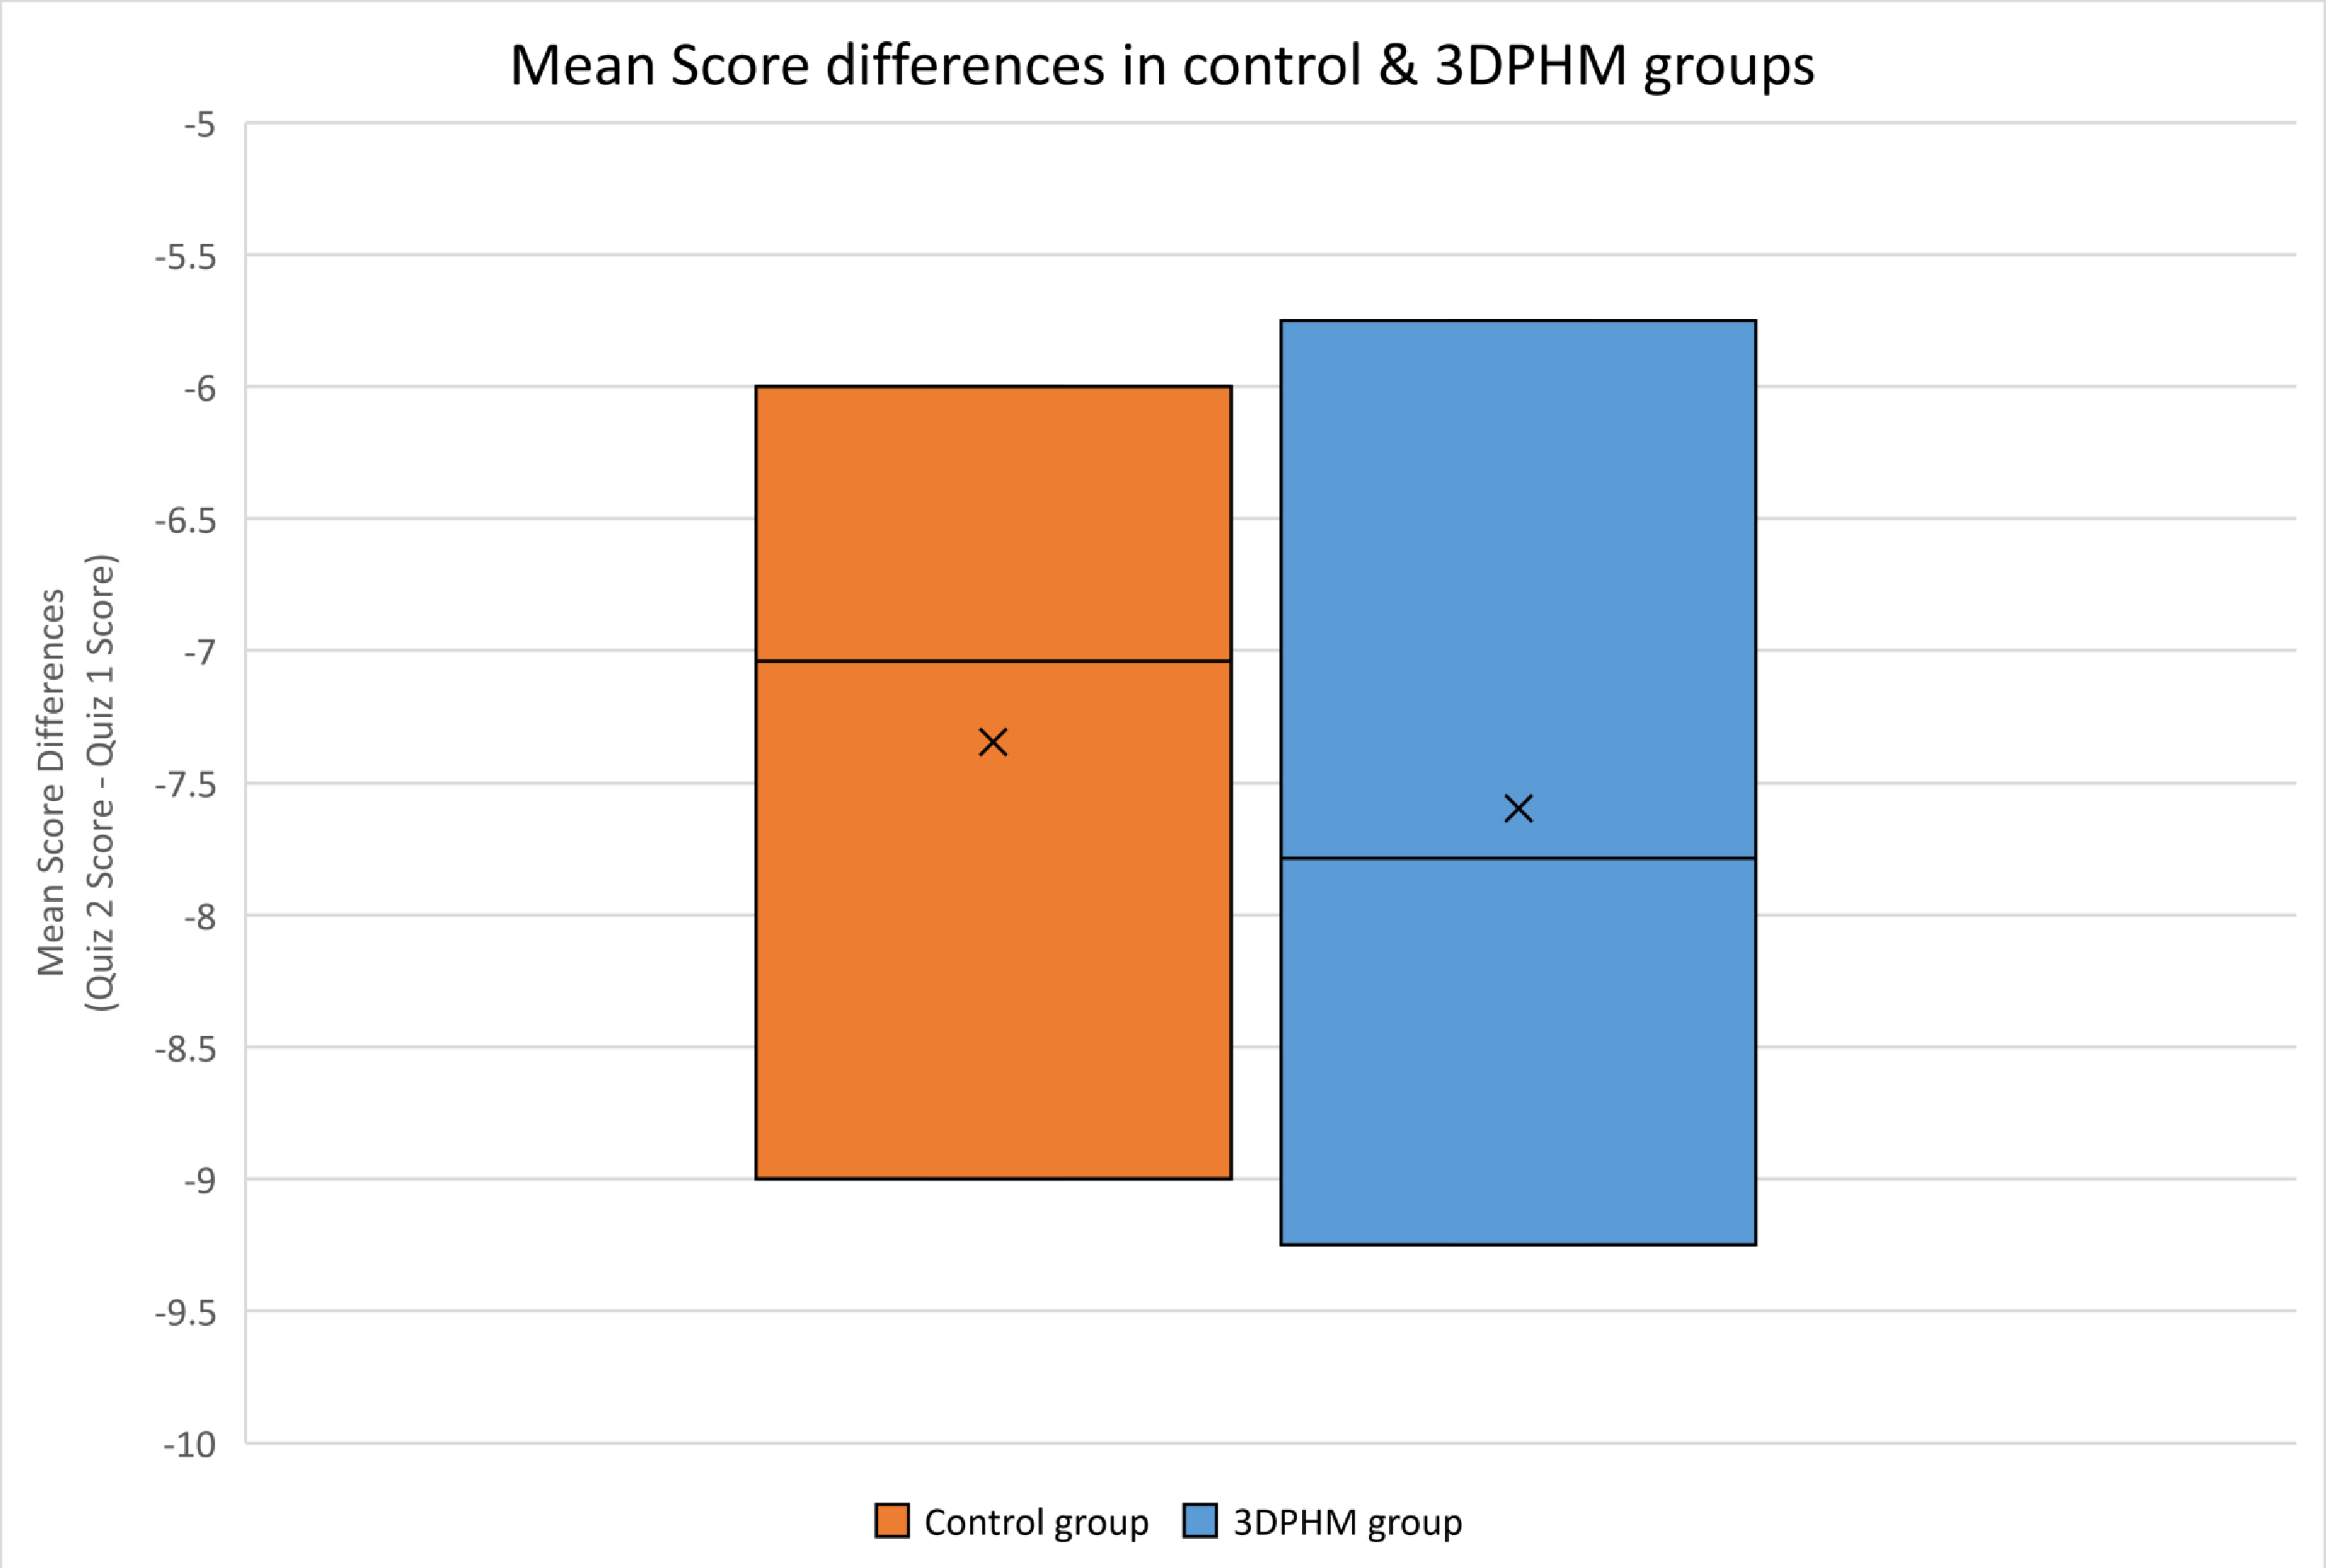

The 3DPHM group experienced slightly higher score difference between Quiz 1 and

Quiz 2, with a mean score difference of 7.79 (

Fig. 6.

Fig. 6.Mean changes in score between Quizzes 1 and 2 (Quiz 2 score – Quiz 1 score) for both control and 3DPHM groups. 3DPHM, three-dimensional printed heart model.

Surprisingly, the 3DPHM group performed slightly inferior to the control group for long-term knowledge retention, even though this was not statistically significant. This is in contrast to another study by Lombardi et al., in which plastic heart models were compared to organ dissection of a sheep heart and virtual dissection using physiology software program, to assess the students’ immediate knowledge acquisition and long-term knowledge retention on normal heart anatomy and physiology. It was found that the plastic model group performed significantly better during the initial exam and the 2-month follow-up exam [20]. This difference in findings might be due to the difference in methods of lecture being carried out in both studies. In Lombardi et al.’s [20] study, the students in plastic model group were allowed 45-minute of hands-on activity with the models as well as within-group discussions after 15-minute of PowerPoint lecture; whereas in our study, the students in the 3DPHM group learned individually and had full 1.5 hour of PowerPoint lecture with different teaching tools incorporated throughout the sessions. The amount of time that they spent on the models might not be enough. On the other hand, the study by Lombardi et al. [20] only focused on normal heart anatomy and physiology, whereas our study focused on CHD, which could justify the difference in findings.